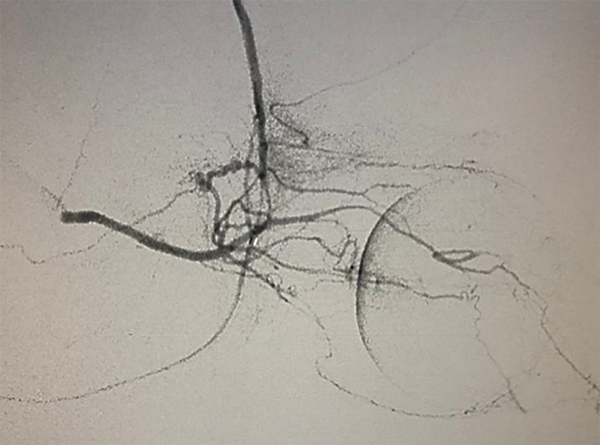

Puede presentarse la situación de observar escaso reflujo hacia la arteria carótida interna durante la adquisición superselectiva, esto no disminuye la efectividad siempre y cuando se logre una correcta opacificación de la coroides y se inyecten las drogas de manera pulsada y suave, según lo descripto por Jabbour et al. Si la maniobra no es satisfactoria se vuelve a repetir este paso. Si luego de dos (hasta tres) maniobras no se consigue cateterizar la arteria oftálmica se asume que no tiene un ostium “favorable” por lo que se da lugar a la siguiente fase de la técnica. Se posiciona el microcatéter en la arteria carótida externa y se cateteriza super-selectivamente la arteria meníngea media (o meníngea accesoria) para visualizar la anastomosis con arteria oftálmica (técnica 2 en 2 completa, fig. 5 y 6).

Fig 6: Cateterización superselectiva de arteria meníngea media (AMM) izquierda bajo road-mapping. Técnica “en dos pasos” o técnica “2 en 2 completa”. Vista lateral estricta. Microcatéter Marathon 1.5.